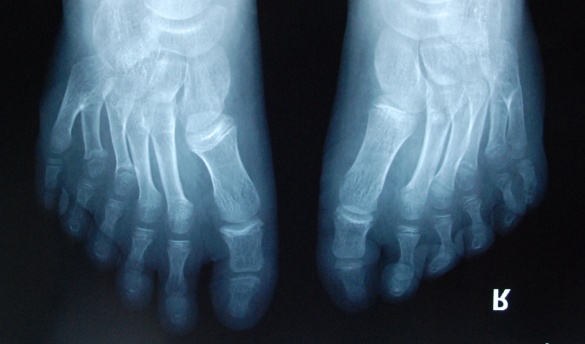

廈門眼科中心小兒眼科修陽暉博士在日常的診療過程中就接診了不少這樣的的特殊家庭,讓其尤為印象深刻的就是一年前接診的BBS綜合征患者。當時來院就診的是一對親兄弟,之前已在多家醫(yī)院做過檢查,因其均有較大散光和斜視,肉眼下眼底檢查未見異常,故外院均診斷為弱視,這也符合眼科門診常規(guī)的診斷邏輯與思維。但由于兄弟倆均有智力發(fā)育遲緩、特殊面容及四肢均有六指和六趾的特異體征引起了修陽暉博士的警覺:會不會是一種特殊遺傳性疾病或綜合征?后續(xù)的檢查結(jié)果進一步證實了修陽暉博士的懷疑---患兒均有夜盲,ERG、VEP及OCT檢查顯示雙眼的視網(wǎng)膜神經(jīng)上皮層結(jié)構(gòu)及功能均明顯異常。由于之前未遇到此種病例,修陽暉博士在診斷一欄寫下視網(wǎng)膜色素變性并打上了個問號,同時留下了病人的聯(lián)系方式。

BBS綜合征(Bardet-Biedl綜合征)是一種主要累及纖毛結(jié)構(gòu)與功能的罕見常染色體隱性遺傳性疾病。纖毛分布于哺乳動物體內(nèi)的大多數(shù)細胞,它是一種廣泛存在于各種細胞表面的細胞器,體型微小但結(jié)構(gòu)復雜、作用強大,能感知細胞外機械和化學信號變化并協(xié)助其轉(zhuǎn)導到細胞內(nèi)部從而引起細胞應答。高等動物的視覺、觸覺、嗅覺、聽覺的傳遞都依賴于體內(nèi)外正常的纖毛結(jié)構(gòu)和功能。因此BBS綜合征常累及全身多個系統(tǒng)和器官,在臨床上主要表現(xiàn)為:視網(wǎng)膜色素變性、智力發(fā)育異常、向心性肥胖、多指(趾)、性腺發(fā)育異常、腎臟異常。除此之外還有許多諸如:語言發(fā)育障礙、聽力異常、嗅覺異常、斜視、白內(nèi)障、散光、牙齒發(fā)育異常、短指(趾)、并指(趾)、肝纖維化、糖尿病、高血壓等表現(xiàn)。